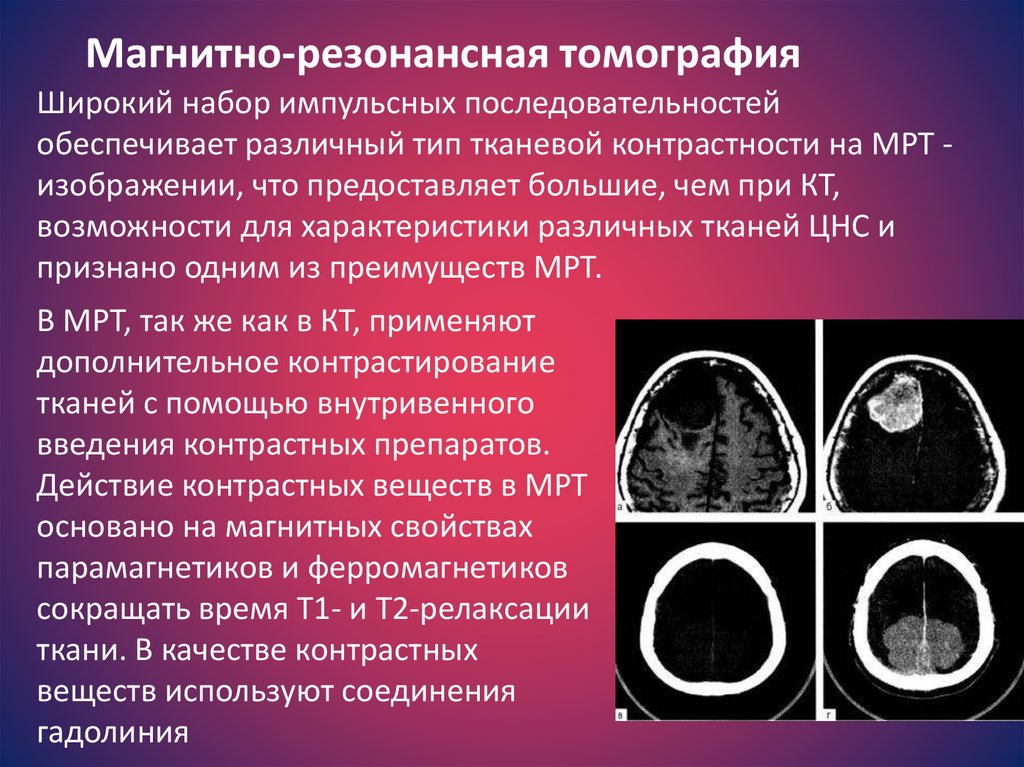

Компьютерная томография в неврологии презентация - 86 фото